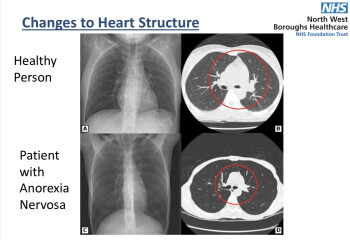

Dd had no idea what she was doing to her body. Would the shock of the effect on the body encourage her to go to a&e? I've got a PowerPoint that lists all the side effects. When I pointed out to dd that she was losing her hair because of the Ed, it gave her a massive wake up call because she'd always had beautiful hair.

Her dad ( not my husband) will not accept it either and thinks we can fix it. I have scren shot one of the messages about heart failure here and sent it to him.

So hard @Snuggleworm. Would these screenshots convince her dad that action is needed?

And these?